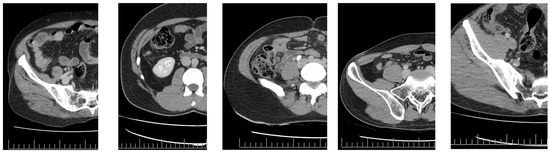

We focused on the region where the appendix is typically situated, which is the right side of the body (left in the figure). Raw images were partitioned into four sections according to the Cartesian plane system. The appendix in the dataset images is situated in the upper-left section and measures 250 × 600 pixels. Appendicitis was excluded from other regions where the appendix could not be located. The image size was therefore reduced from 1255 × 515 pixels to 250 × 600 pixels for analysis (Figure 4).

Figure 4. The image section used for deep learning (the red square).